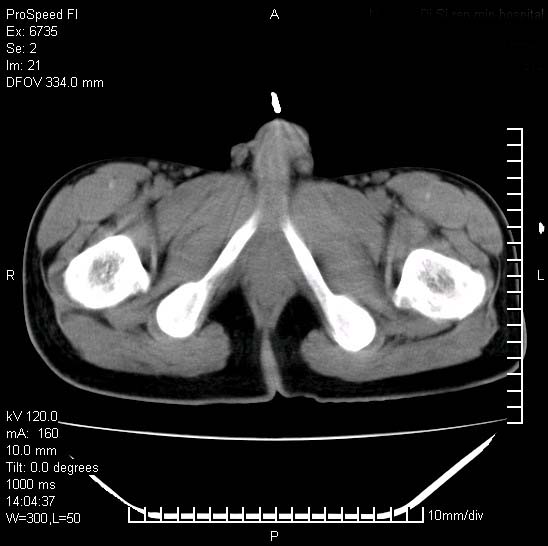

患者自诉胯部疼痛两年余,在当地服用中药,半月前至本院考虑骶髂关节结核,给予抗痨治疗。现发展至右下肢疼痛明显,活动受限,以膝关节处明显,拍膝关节平片无明显异常。

两侧骶骼关节改变,考虑强直性脊炎

左侧骶髂关节面限局性骨破坏,边缘硬化关节腔见钙化物;不出外tb

右侧骶髂关节也有类似改变,只是较左侧轻,首先考虑强直性脊柱炎,不除外结核,建议作hla-b27检查。

典型强脊炎改变,髋关节亦有累及

符合强直性脊柱炎表现。